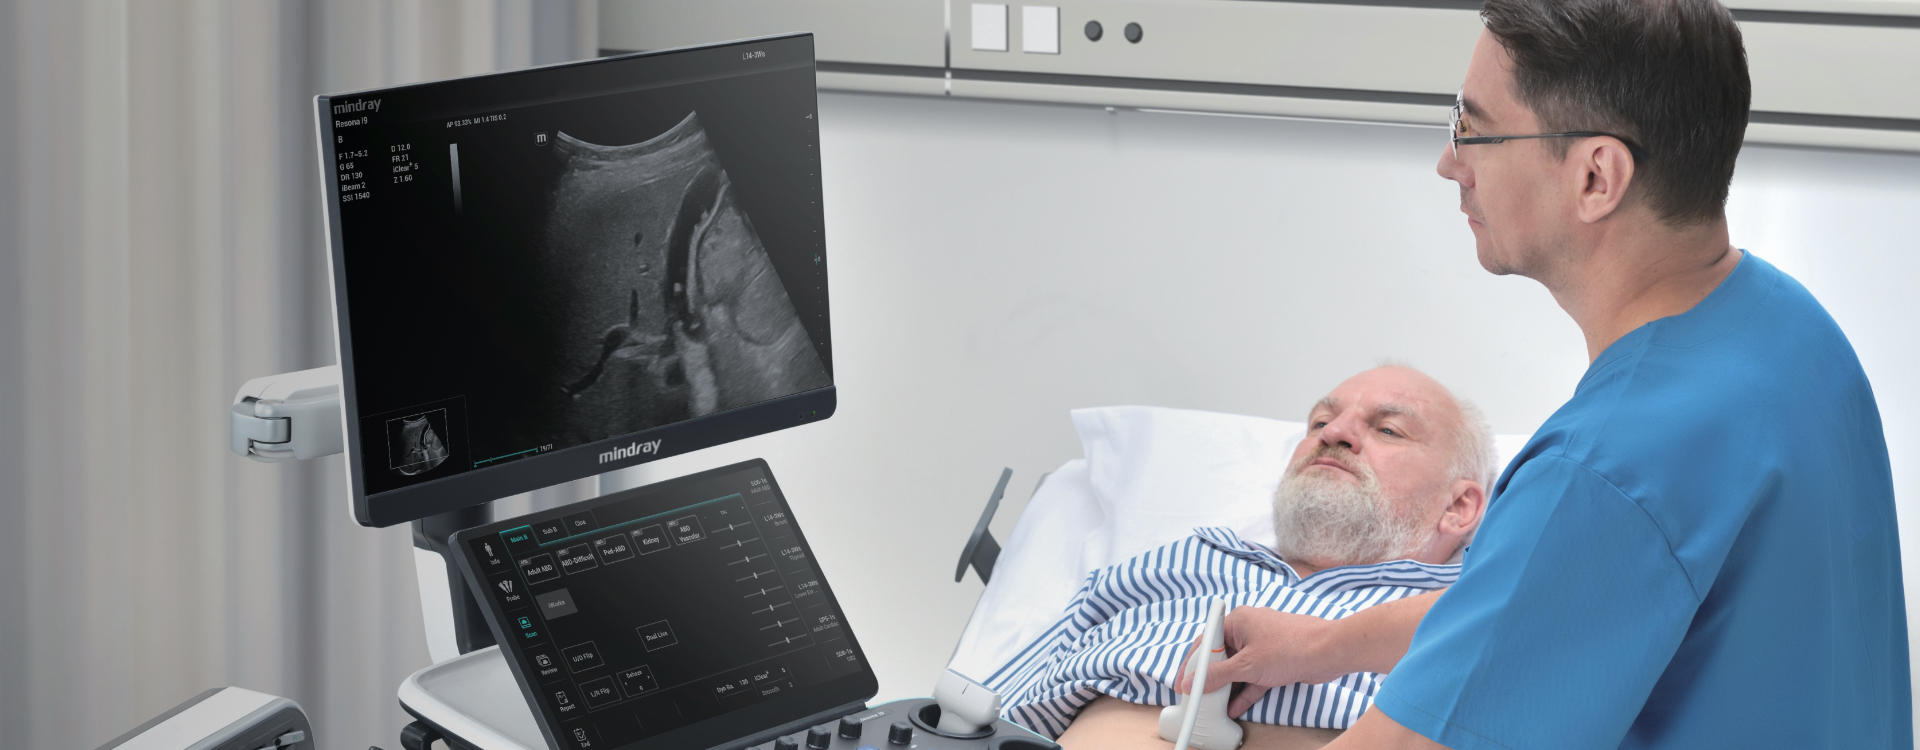

Prepare to be greeted by an ultrasound system design that is truly one-of-a-kind. Take advantage of its latest innovative features to minimize your fatigue during scans.

Resona I9 provides comprehensive clinical solutions for dedicated applications. Based on in-depth insights into different clinical scenarios, it delivers innovations that give users extreme clarity, outstanding intelligence and enhanced diagnostic confidence.